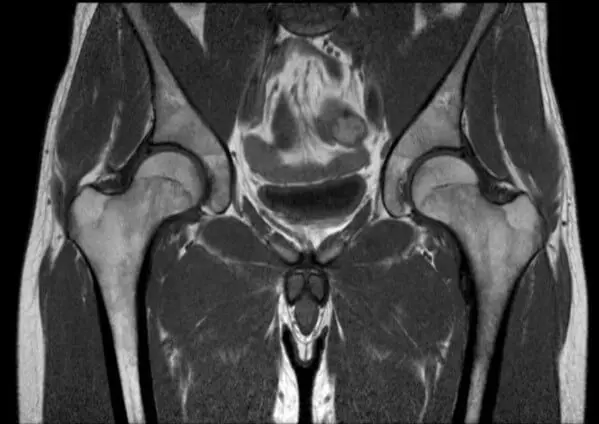

МРТ кульшового суглоба

Без МРТ важко обійтися при діагностиці болю в області тазостегнового суглоба. Оскільки більшість скарг з боку тазостегнового суглоба – це біль. Але, біль може бути не тільки наслідком артрозу тазостегнового суглоба, але і його запалення. Якраз всі запальні процеси прекрасно видно на МРТ кульшового суглоба. Разом з тим, не можна забувати, що рентген – це «золотий стандарт» у вирішенні питання наявності та ступеня артрозу тазостегнового суглоба.